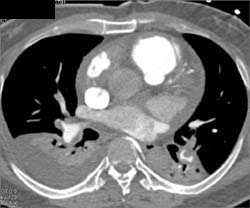

Enlarged Pulmonary Artery With Narrow Left Mainstem Bronchus